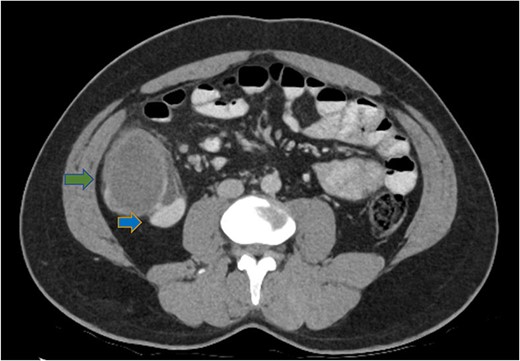

A number of differential diagnoses were considered including neoplastic and infectious pathologies such as latent TB, hydatid or amoebic cyst. A subsequent colonoscopy showed a submucosal semi-pedunculated lesion in the ascending colon measuring greater than 50 mm (Fig. 3). Biopsies were histologically nonspecific. As the patient was symptomatic of this lesion, and moreover as a malignant process could not be excluded, he proceeded with a surgical resection.